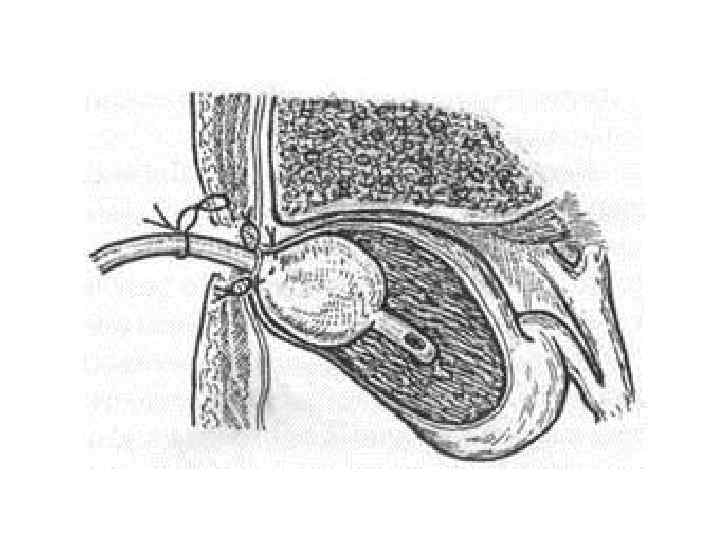

УЗИ бақылауымен транскутанды холецистостомия Қарсы көрсеткіштері: перитонит, гангренозды холецистит, «фарфоровый» холецистит

Ашық холецистостомия